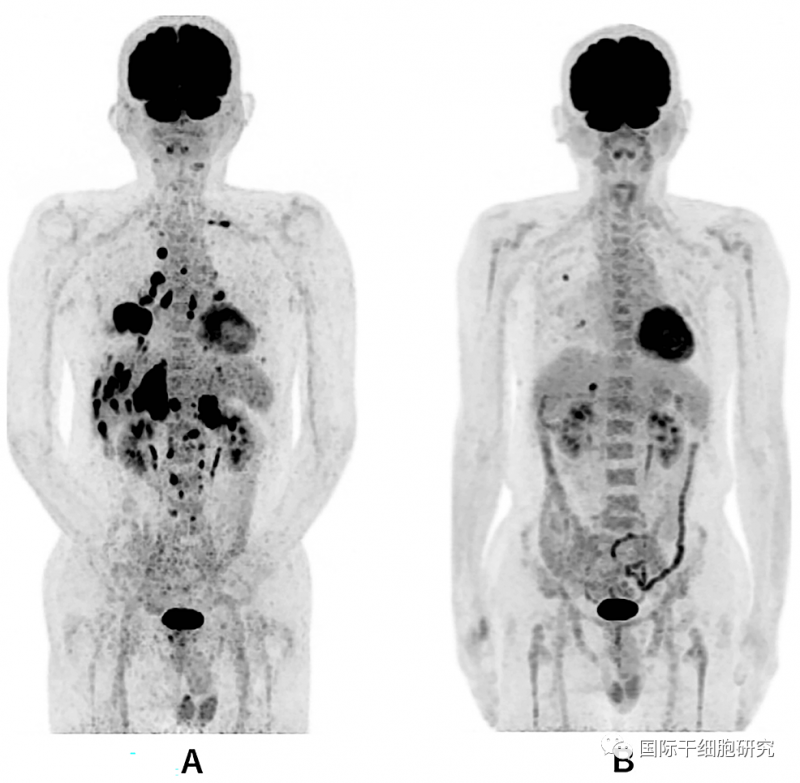

图1 全身PET-CT对比

图片A(诊断时的全身PET-CT):示右下肺原发肿瘤,伴多发性双侧肺内转移、双侧肾上腺转移、多发性肝转移、多发性骨转移。

图片B(治疗第479天的全身PET-CT):示右肺有2个小转移(直径为1.0cm),肝脏有1个小转移(直径为1.7cm)。